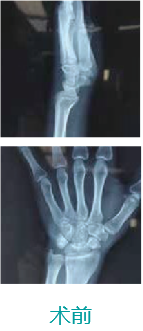

天玑II 辅助腕舟骨骨折经皮内牢靠术

基本情形:患者女,,,,,58岁,,,,,腕舟骨骨折

机械人辅助优势:天玑II应对不规则骨骨折,,,,,可通过机械臂最后360°追踪定位,,,,,为四肢骨折提供微创治疗计划。。。。。。

病例泉源:北京积水潭医院